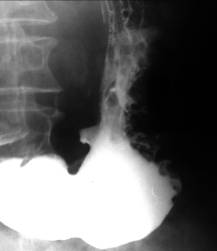

Ulcere jeune bulbaire . Image

TOGD en OAD normale et expose avec compression

region bulbaire |

Aspect en treffle une ulcere

bulbaire . Image TOGD baryte en OAD |